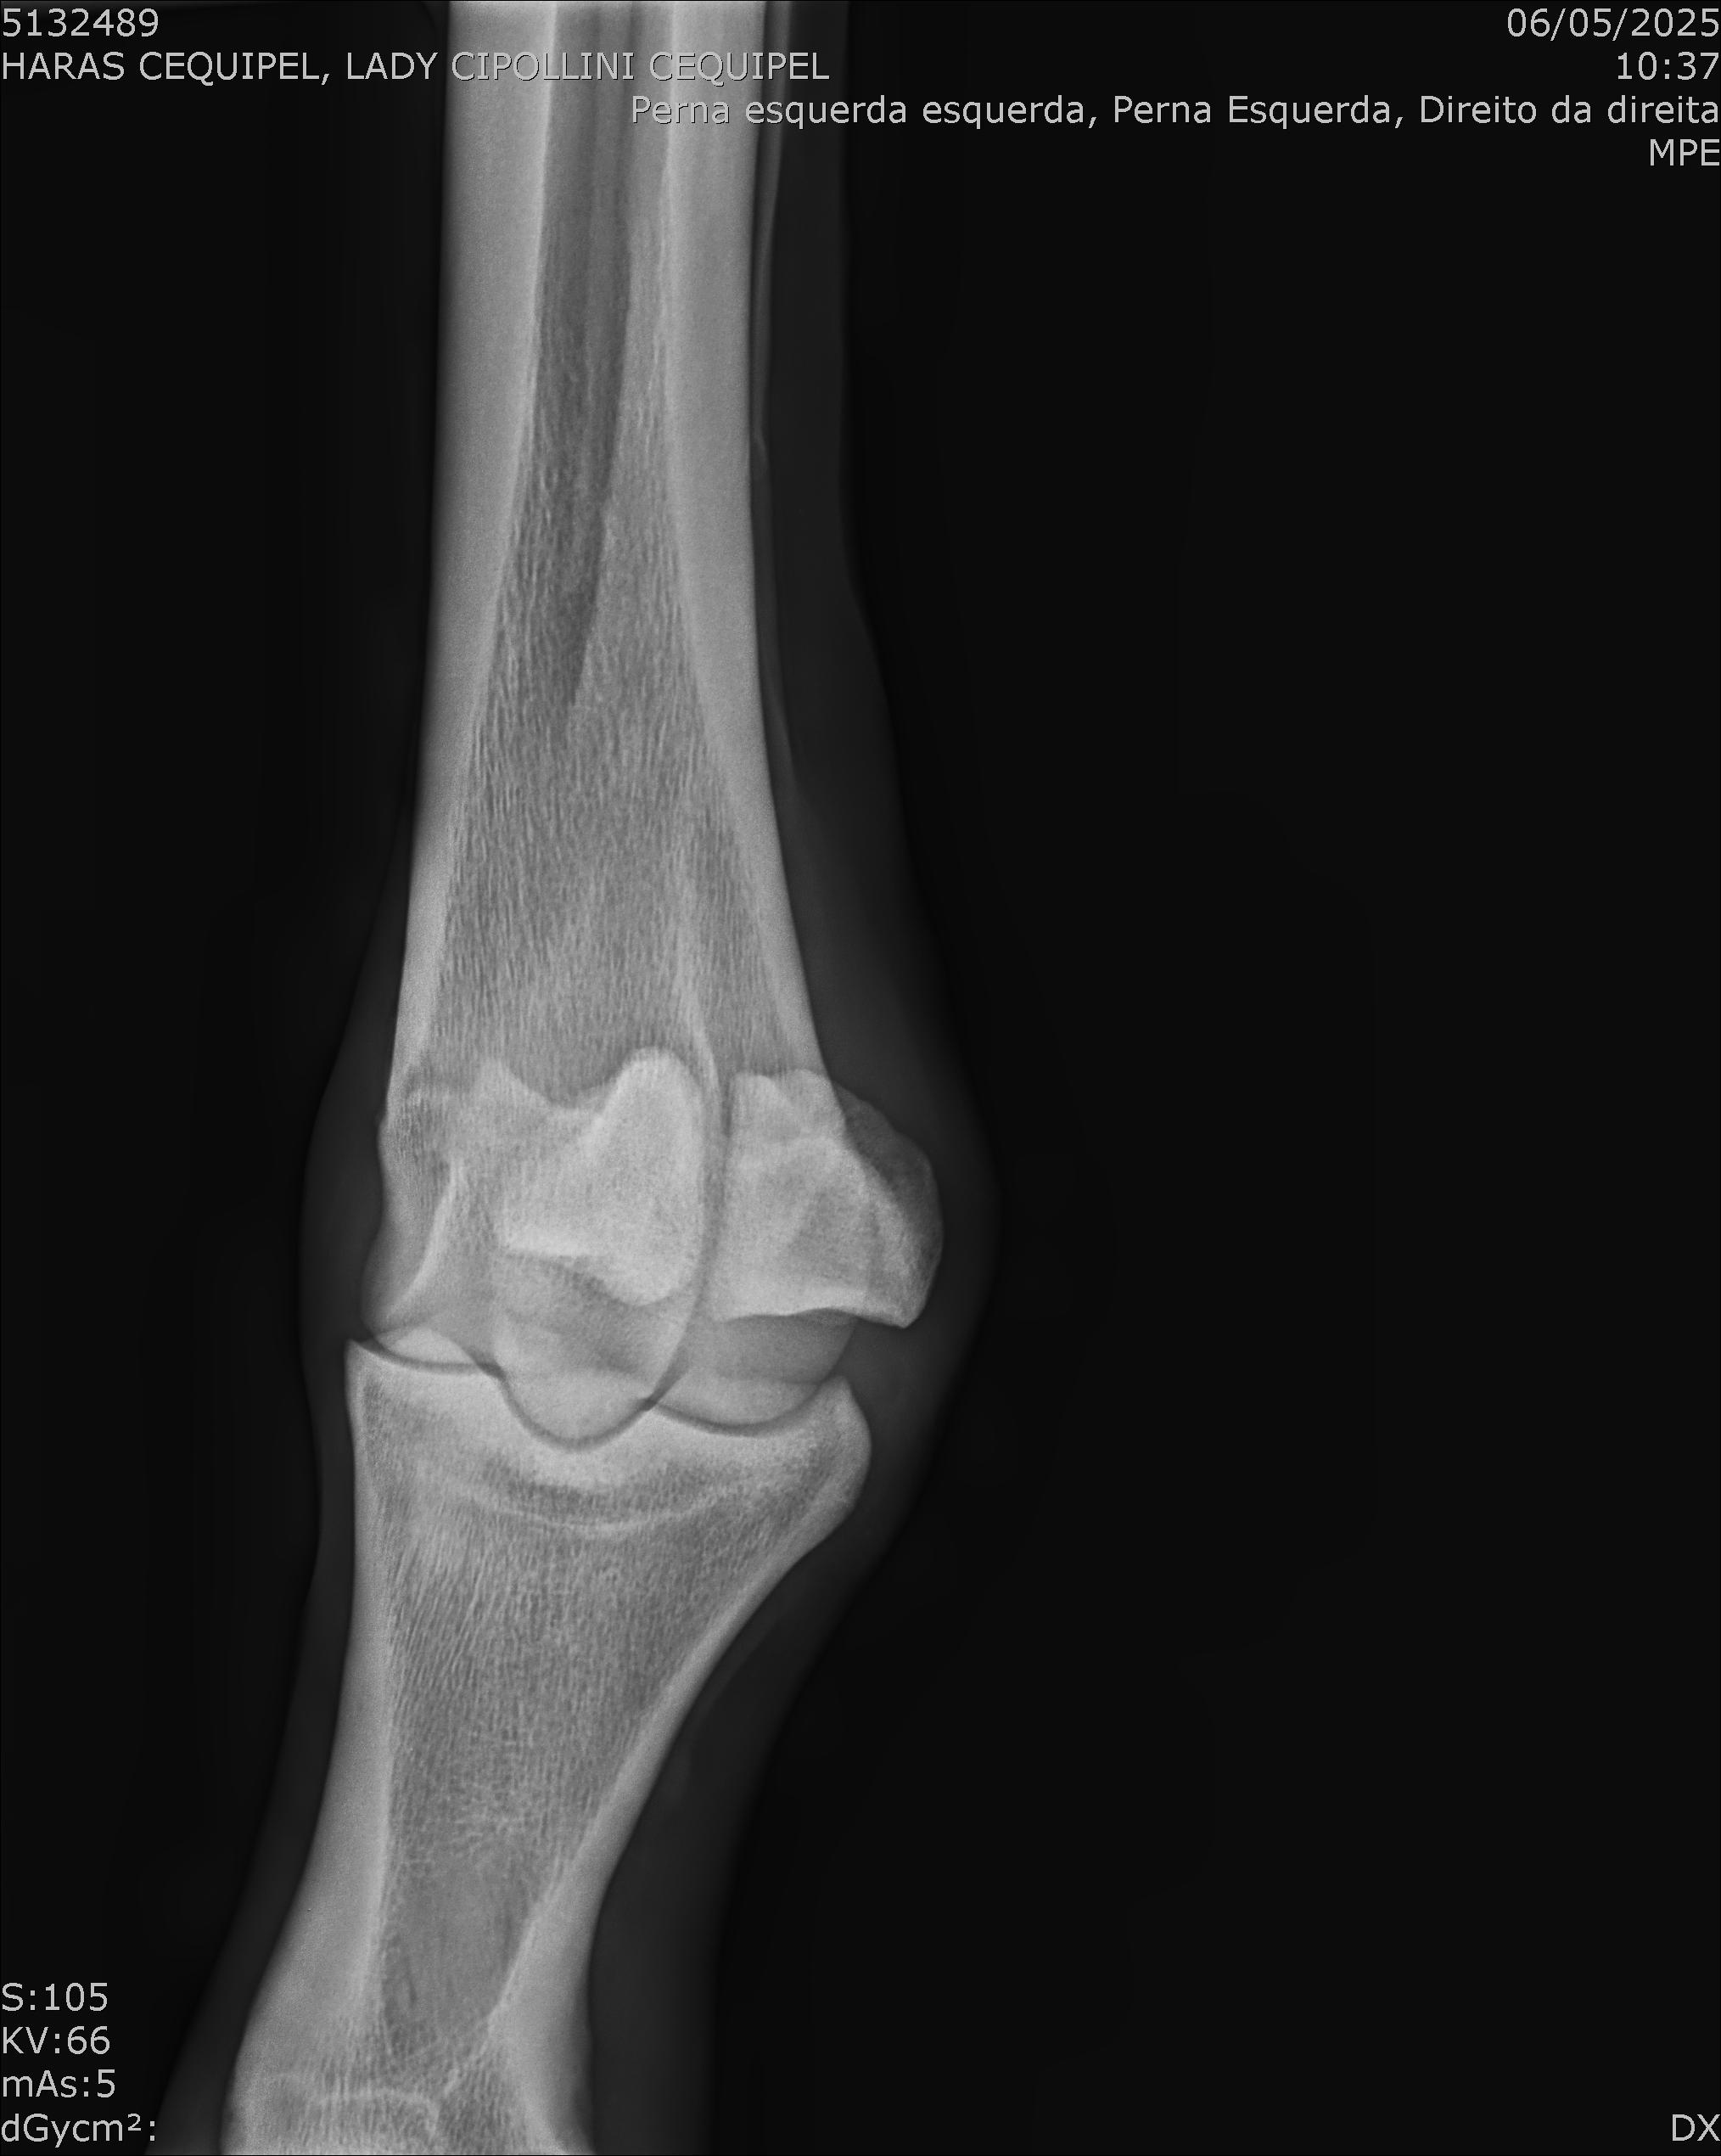

:: RAIOS-X DO LOTE